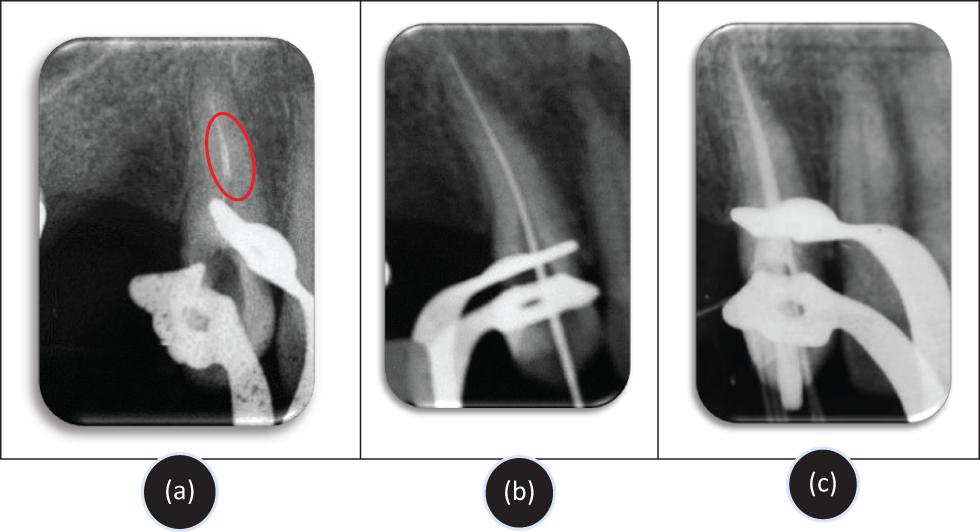

A 30-year-old male patient presented to the Department of Conservative Dentistry-Endodontics at the CCTD CHU Ibn Rochd Casablanca for the management of a separated endodontic instrument lodged in the right upper canine. His medical and dental history were unremarkable. Radiographical examination revealed the instrument fracture location between the middle and apical thirds of the root canal (Fig. 2a).

Fig. 2. (a) Pre-operative radiograph: Separated instrument located between the middle and apical thirds of the canal; (b) Working length radiograph after removal of the fragment using the braiding technique; (c) Control radiograph after root canal obturation.

- SI extraction with braid technique and working length determination: The Hedstrom files were twisted together, entangling the fractured instrument, and then withdrawn as a single unit. An X-ray confirmed the complete removal of the instrument and determined the working length (Fig. 2b).

- Final obturation: The tooth was permanently filled with gutta-percha, completing the endodontic treatment (Fig. 2c).